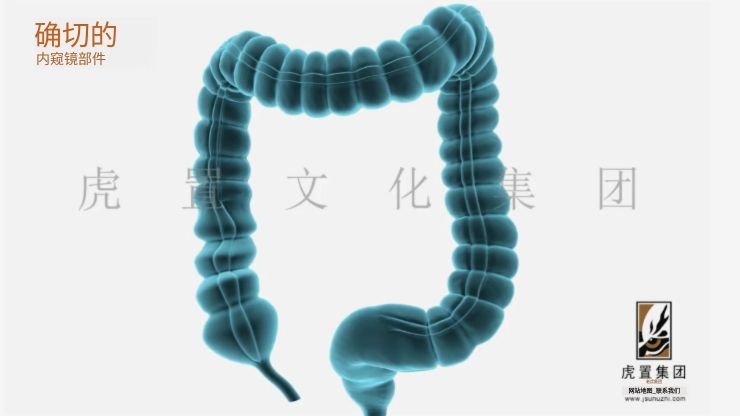

深耕于数字设计及展示领域的虎置文化集团正努力成为全球知名的数字设计及展示服务商,创办至今20年,旗下五家子公司,是集设计、展示、施工于一体的综合运营服务商。集团旗下控股上海虎置文化集团有限公司、江苏虎置文化传播有限公司、上海比筑视觉艺术设计有限公司、上海虎置建筑设计有限公司和江苏艺派数字科技有限公司四家子公司,为不同行业客户提供基于文化创意服务的整体解决方案。

致力于:全案设计、展馆展厅、三维动画、卡通动漫、影视广告、3D效果图等综合服务,设计包括:建筑设计、景观设计、规划设计、展馆设计、室内设计、 BIM设计;展示包括:三维动画、全息展示、影视广告、数字展馆、二维动漫、3D仿真效果图、VR&AR等;施工包括:展馆展厅、室内装饰、幕墙工程、亮化工程。